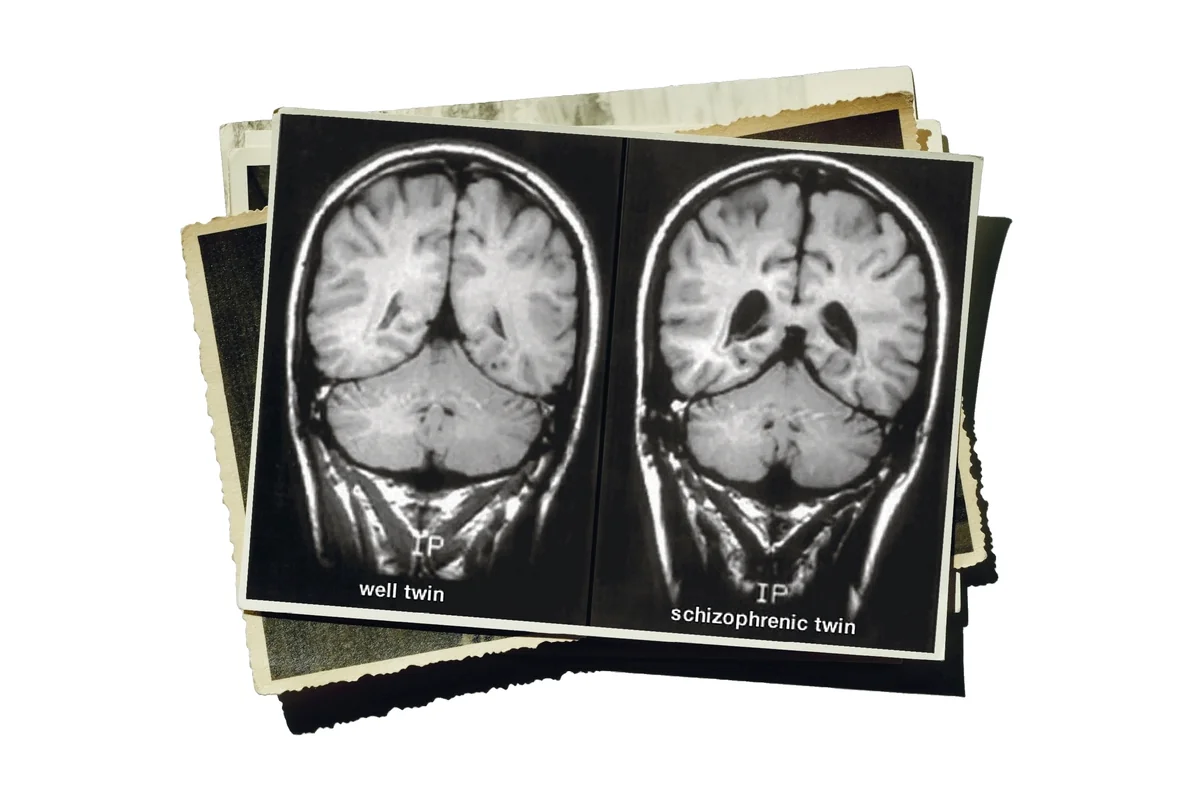

Diese Hirne von Zwillingen, von denen einer schizophren war, waren grundlegend für die Anerkennung der neurobiologischen Ursachen Foto: Fuller Torrey, The Stanley Medical Research Institute, Montage: taz